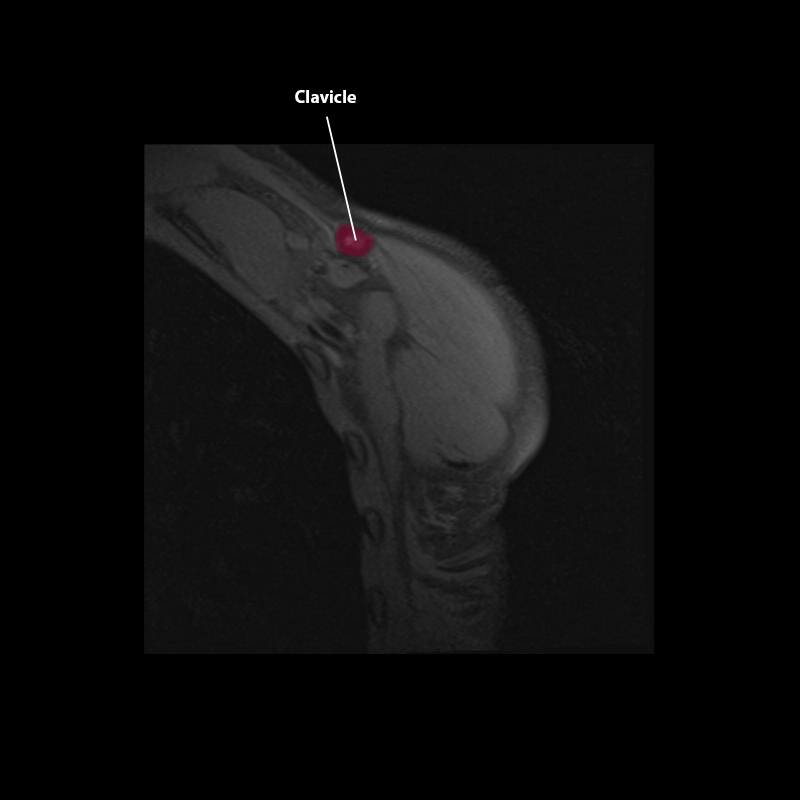

Shoulder MRI Anatomy